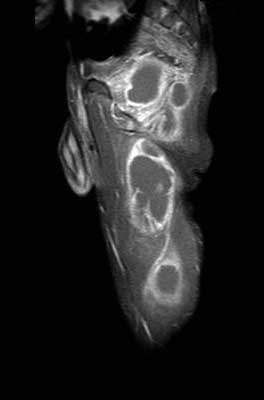

[Ortho] Остеомиелит таза?

Хорошо когда есть микробиолог - подсказка. Аспират направили еще и на PCR (polymerase chain

reaction) с подозрением на то, что и нашли - TB. Чувствителен к рифампицину. Теперь

подключаем фтизиатров? Какой есть опыт, господа? P.S. А если нет PCR - сиди и гадай, что там?

Имя     : mri 51203977.jpg